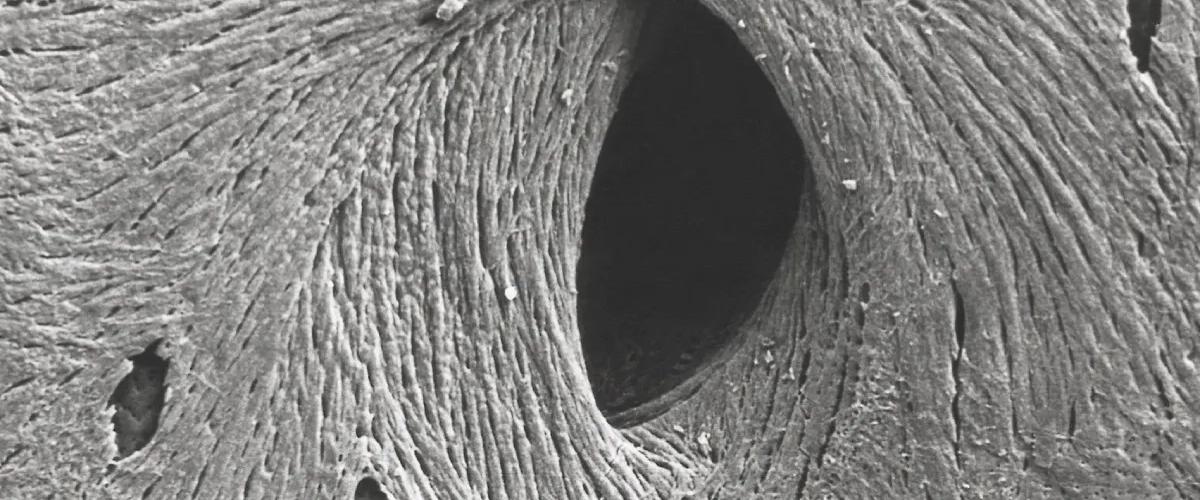

При разработке импланта ученые использовали полимер полиэтилакрилат (ПЭА), поскольку ранее было установлено, что он взаимодействует с белком фибронектином. Этот белок способствует адгезии и росту клеток, образуя своеобразные сети на поверхности ПЭА. В рамках своих экспериментов ученые обнаружили, что добавление белка rLTBP1 заставляет его слипаться с фибронектином, а это, в свою очередь, помогает прилипнуть еще одному белку под названием TGF-β1.

Белок TGF-β1 стимулирует факторы роста для производства новой костной ткани. Теперь его упаковали в белковый комплекс, чтобы запустить регенерацию кости в нужном месте в нужное время, сообщает Interesting Engineering.

Ученые покрыли имплант ПЭА новым белковым комплексом и ввели мышам.

Лечение обеспечило полную регенерацию костного дефекта даже большого размера. Побочных эффектов не зарегистрировано.